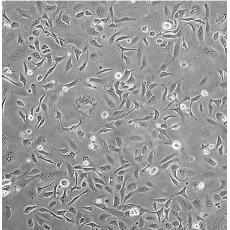

產(chǎn)品名稱 SK-OV-3 [SKOV3]

中文名稱 人卵巢癌細胞

組織來源 卵巢漿液性囊腺癌;腹水轉(zhuǎn)移;女性

細胞種屬 Homo sapiens, human

生長特性 adherent

培養(yǎng)基 McCoy's 5A+10% FBS+1% P/S

形態(tài)特征 epithelial

細胞描述 SK-OV-3 cells are resistant to tumor necrosis factor and to several cytotoxic drugs including diphtheria toxin, cis-platinum and adriamycin.